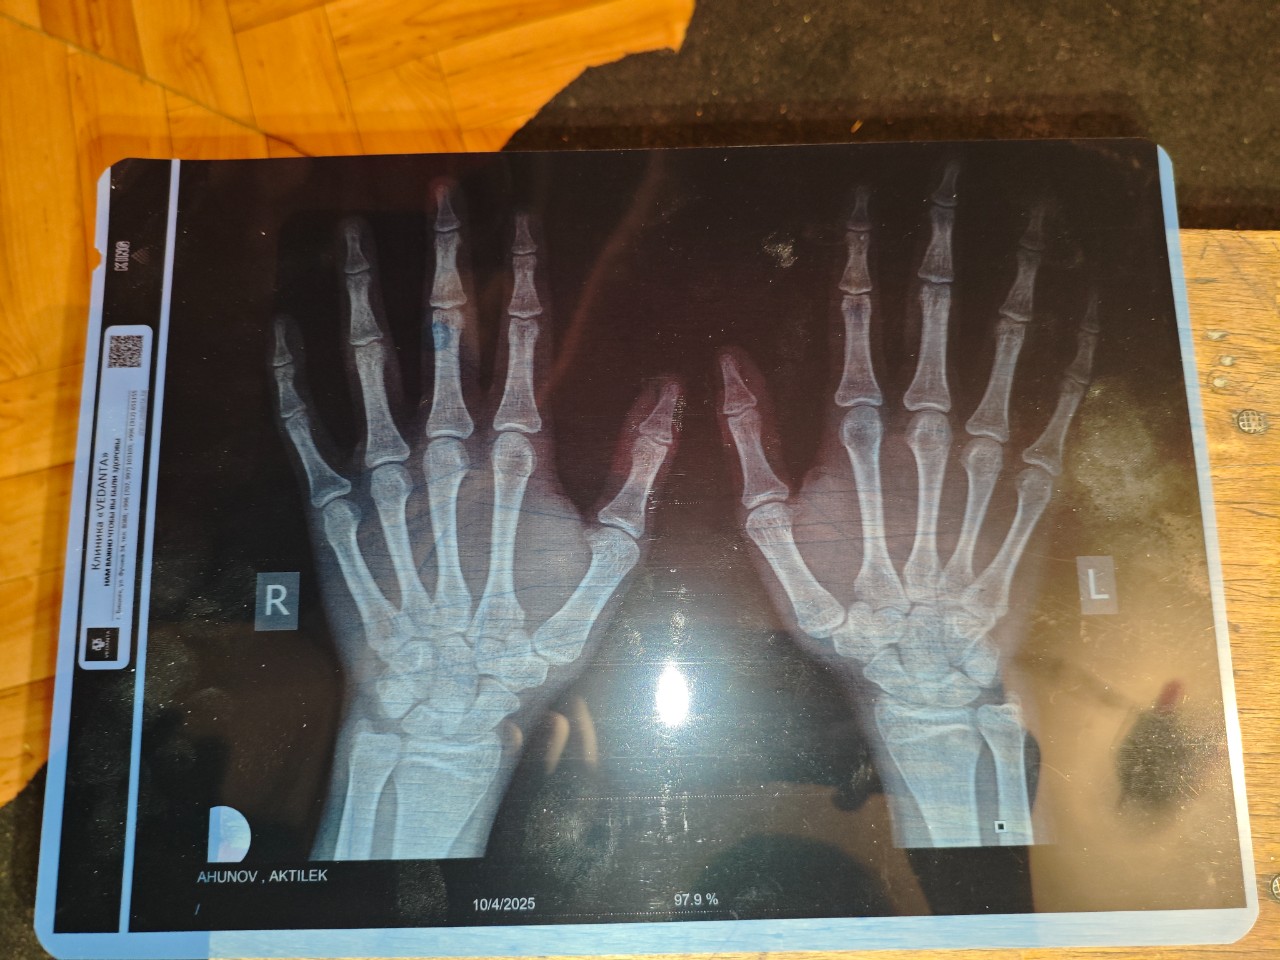

Возраст: 16 лет и 8 месяцев.

Здравствуйте, с детства был догоняющим по росту по сравнению с сверстниками. Сейчас мой рост когда сам измерял (правильно) 163-166. У эндокринолога был, она сказала, что у меня 160 рост и вес 46. И суть всего этого в том, что я бы хотел узнать, можете ли по фотографии, которые я прикреплю ниже определить мой костной возраст и закрыты ли зоны роста? Мой отец начал активно расти после 10 класса. Он ростом 181 - мама 165-169.